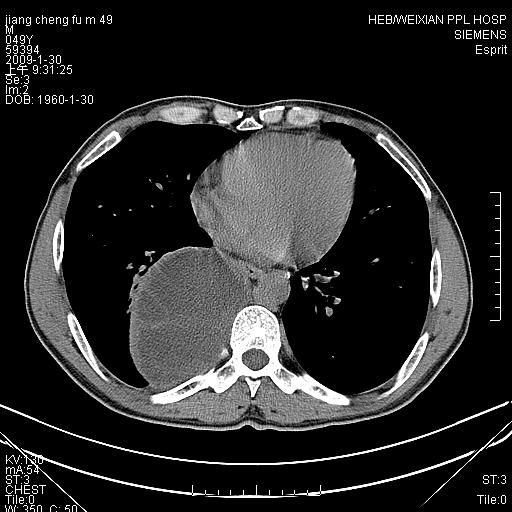

男性,49岁,主因胸痛,右肺呼吸音低。胸片提示肺占位

考虑右侧脊柱旁沟囊性病变。1:支气管囊肿或食管囊;2:神经源性肿瘤。

右后纵隔囊性占位;考虑为:1)淋巴管囊肿。2)食管囊肿。建议:进一步检查。

右后纵隔囊性占位,建议先做增强,后做穿刺活检。

在分析这个病变时,首先病灶边界清晰,但其内密度不均匀,有条索状状实性成分,肿块的外侧壁亦呈一不均匀的厚壁改变,因此支气管囊肿的可能性不大。主要考虑神经源性肿瘤(主要考虑神经鞘瘤,因为它囊变的机率比较高),其次考虑肺膈离征,行增强扫描如发现来自胸主动脉供血动脉血管可确诊。

患者已做手术,病理家属不甚清除,只说良性病变。手术完全切除,术后复查未见明显异常。

考虑右侧脊柱旁沟囊性病变,囊骨有分隔,囊壁较厚。1:神经源性肿瘤;2:食管囊肿或淋巴管囊肿。支持!

囊状肿块内有线样软组织分隔,支气管囊肿及食管囊肿可不考虑。我考虑:1、囊性肺膈离征(需要增强扫描来排除)。2、神经鞘瘤。3、淋巴管囊肿。

可惜了,仍然是不知道最后的结果,依照楼主所说家属的反映,‘良性病变,完全切除’,还是考虑神经纤维瘤可能性大一些